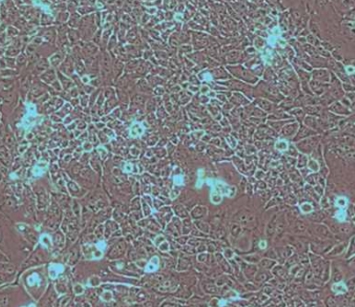

2. 细胞名称:HPAC(人胰腺腺泡上皮癌)

7. 细胞类型:上皮细胞样

8. 生长特性:贴壁生长

1. 背景特征:来源于胰腺腺泡上皮癌组织,典型的上皮细胞样形态,具有明确的受体表达特征。

2. 生物学特性:在裸鼠体内可形成肿瘤,组织学特征与原始肿瘤相似;在塑料培养皿中集落形成效率为64%;在琼脂糖中集落形成效率为3.2%;表皮生长因子受体(EGF)表达;糖皮质激素受体表达;角蛋白(keratin)阳性;波形蛋白(vimentin)阴性;嗜铬粒蛋白A(chromogranin A)阴性;倍增时间:23-44小时。